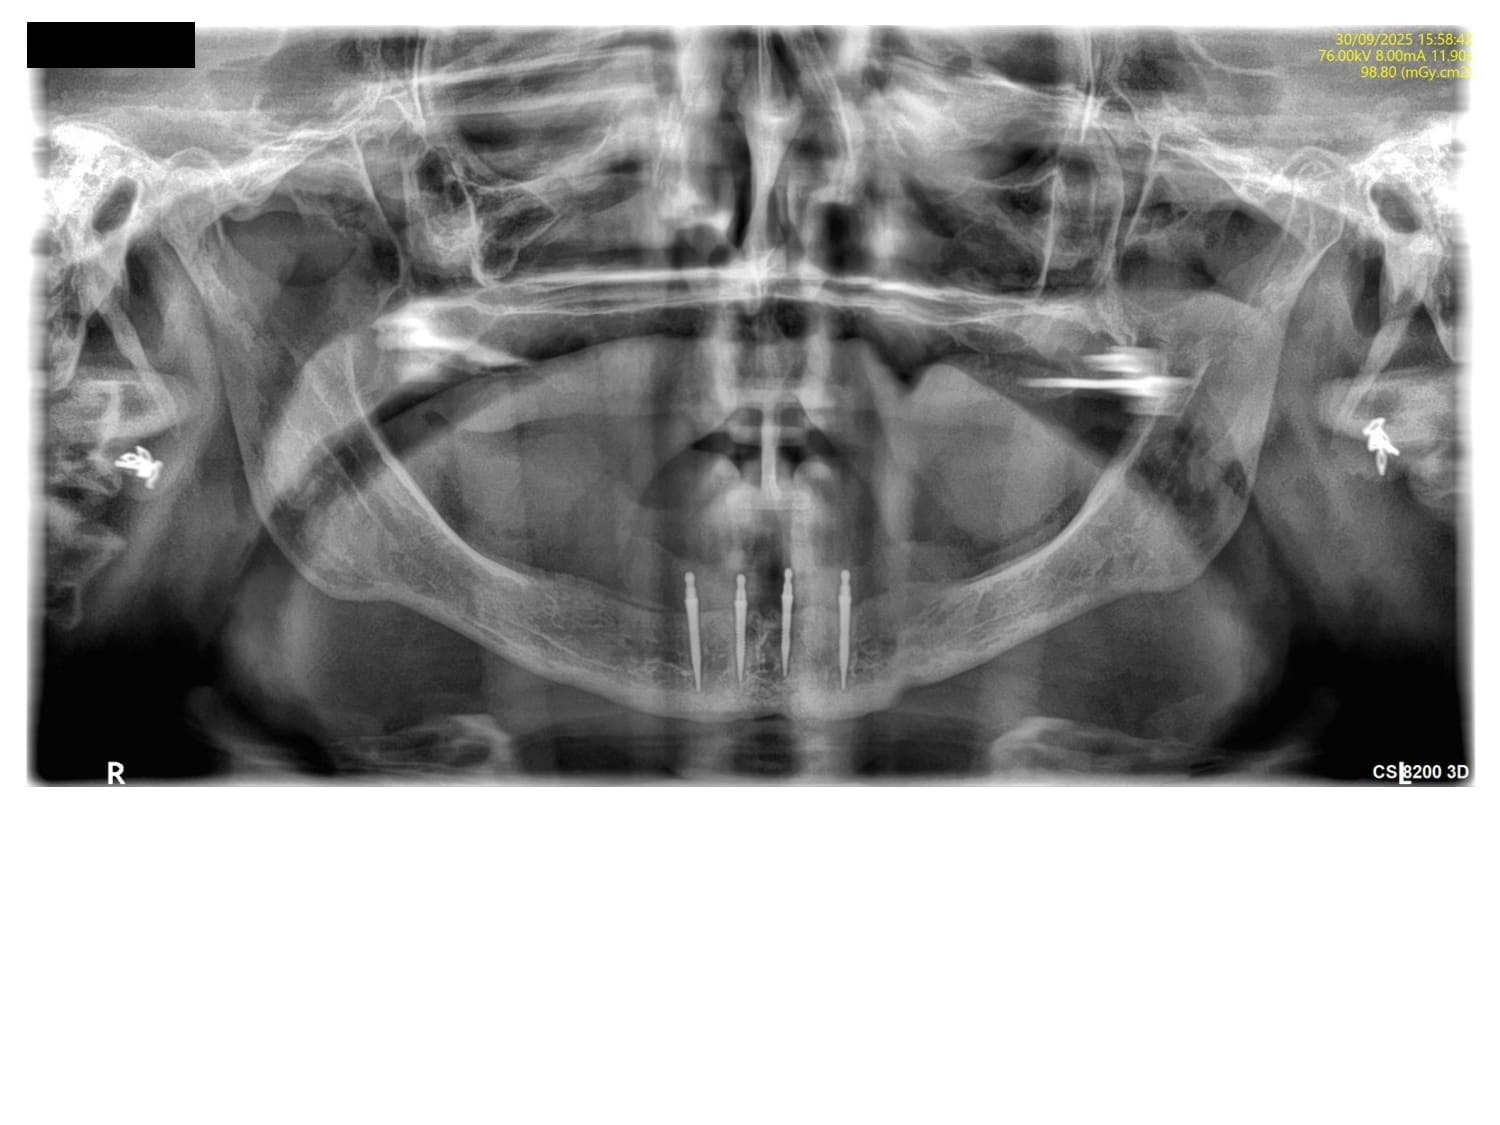

IMPLANT 36 DECORMIS MONIQUE.jpg